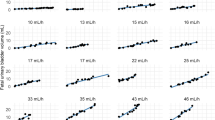

The SD for the estimated HFUPR (SDHFUPR) depends on the method of bladder volume estimation (SDVOLUME), the magnitude of the HFUPR and the number and time points of bladder image capture. The derivation was presented in Formulas 6 and 7 in the Statistics section. The new constants c and d in Eq. 7 are crucial for the further derivations (Fig. 2; Table 1).

This calculation of the HFUPR measurement error (SDHFUPR) was based on images captured at five, 10, 15, 20, 25 and 30 min after an emptying phase, when applying the ellipsoid and the sum-of-cylinders method (different SDVOLUME). The SDHFUPR ranged from 31 to 12% for the ellipsoid method and from 20 to 5% for the sum-of-cylinders method for HFUPRs of 5–40 mL/h

A starting point for the present paper is the linear relationship between bladder volume and the measurement error: SDvolume = a + b × volume. This relationship has been thoroughly documented in three previous studies [2, 3, 4]. When all the cases in these studies are included, the distribution of the SD and residuals supports a linear relationship, which is a prerequisite for using a linear regression function [13] (Figs. 3 and 4).

The SD was calculated when estimating the bladder volume of 120 fetuses. Different methods were used, which gave rise to 222 relationships between SD and bladder volume. The maximum and minimum bladder volumes were 80.5 and 0.1 mL, respectively. The distribution of the SDs supports a linear relationship